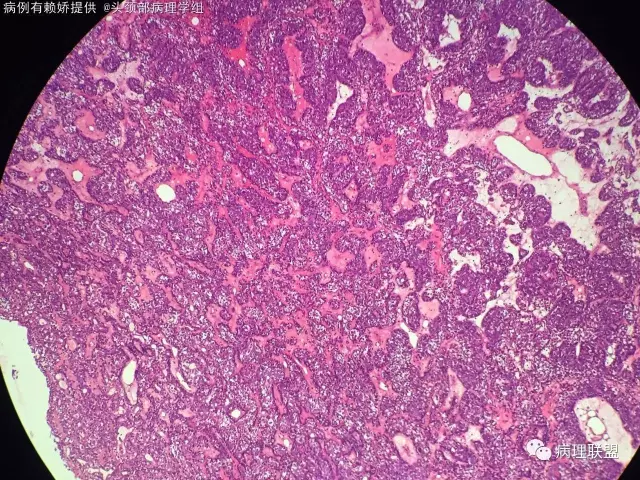

男,54岁,后颈部肿块10年(病例由赖娇 提供,致谢!)

小汗腺螺旋腺瘤

@梅宜兼 本例明显呈上皮巢排列,肿瘤由两种细胞构成外层呈栅栏状排列细胞小核染色深,另一种为咯略大淡染隐约可见小核仁的腺上皮细胞!间质可富裕血管,水肿及少量基底膜样物质!另外还有个特点散在淋巴细胞!该肿瘤肉眼看切片给人第一印象像个淋巴结!

有时候看上去像圆柱瘤